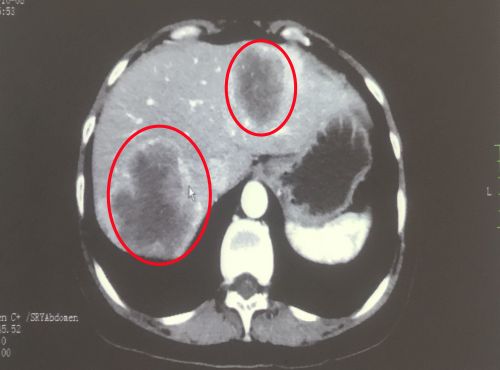

治疗前影像显示:肝脏有多发转移灶(红圈内)。